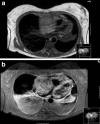

Cardiac metastasis of malignant melanoma: a case report

The heart is regularly involved in metastatic neoplasms with cardiac metastases being found in up to 20 % of autopsies. We present a case about a 42-year-old Caucasian female with a fatal metastatic melanoma to the heart. The five- year survival rate for stage IV melanoma (melanoma with metastases to other organs) is 15 to 20 %. If patients with malignant melanoma present with new onset of cardiac symptoms, clinicians should always be aware of the possibility of cardiac metastases and perform further investigations.